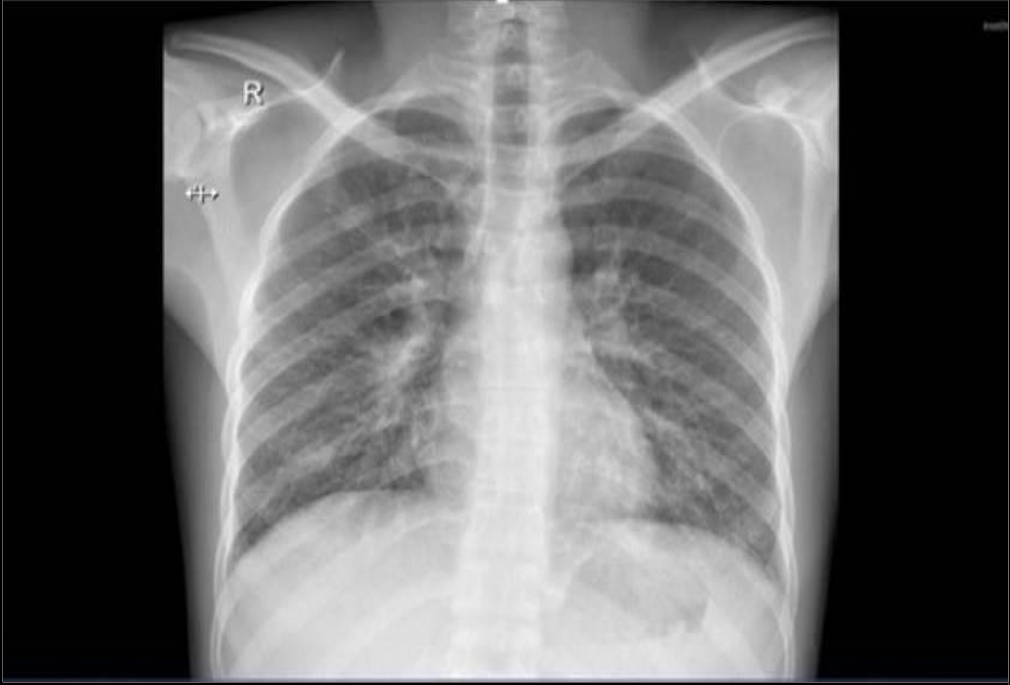

Chest X-ray

Suggestive of active pulmonary TB

(“18 Nov 2024”) Inhomogeneous opacity with a cavity formation is seen in right mid zone in para hilar region.

He started with the intensive phase of 4 medications for the 6 months anti tuberculous regime; his cough had improved, as well as follow- up lab test of CBC, electrolytes-renal functions and LFT were all normal, while CRP dropped to 8.7 and ESR to 10. The repeated chest x-ray, performed 2 weeks after initiating therapy, demonstrated mild improvement of the initial findings. The Mycobacterial culture confirmed sensitivity to both Rifampicin and Isoniazid, which supports the continued use of the standard first-line anti-TB regimen.

(“05 Dec. 2024”) Slight improvement of the opacity is seen